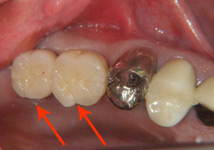

| 右下奥に義歯を入れられておりましたが、うまく噛めずにインプラントにしました。現在は満足して食べられると患者様に感謝されました。 |

| インプラントを植立したところ |

インプラント治療完了 |